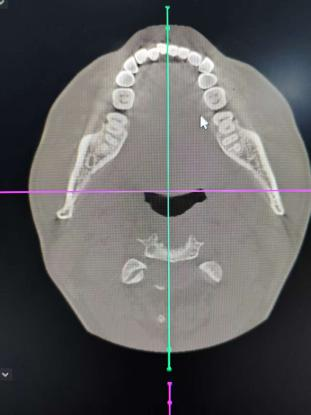

口腔CT,也就是口腔锥形束CT(CBCT),是目前国际最先进的口腔科专用检查设备,是利用锥束投影,借助X线扫描检测部位,然后将所得到的数据在计算机中重组、成像,可以直接观察检测者反应颌面组织三维空间结构,应用范围较广,牙周病科、口腔颌面外科学、种植牙、正畸学等科室都需要借助这项检查来为病情诊断、治疗计划以及恢复情况来提供客观依据。

3.影像后期处理功能强大,彩色三维重建从上下、左右、前后各个方向任意旋转,可以任意层厚、 任意层距、任意切面,多方位、多角度的观察病变。

4.适用范围更广、诊断更加准确。牙齿种植术前骨量及密度分析,埋伏牙的准确定位,复杂的根尖周病变诊断,阻生齿拔除方案的详细制定,颌骨囊肿范围的确定, 颞下颌关节骨质的检查等。

新野县人民医院是我县唯一一家拥有专业口腔影像设备的公立医院,引进的多功能CBCT,具有口腔全景摄影、头颅定位测量摄影、CBCT三种检查功能,对于牙周病、根管治疗、囊肿、阻生齿的检查诊断,种植牙手术前后的诊断分析,口腔正畸对牙颌畸形的诊断与治疗分析,颌骨外伤检查与诊断具有良好的指导意义。